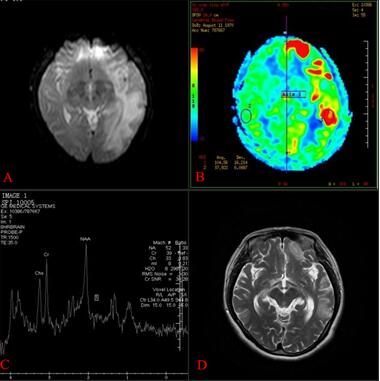

既往体健,家族中无遗传病史。患者于2017年12月病情加重,在广东三九脑科医院神经内一科住院治疗。入院查体:神志模糊,左上肢肌力4级,左下肢肌力1级,右侧肢体肌力1级,四肢腱反射减弱,双下肢病理征阴性。头颅MR(A图)提示左侧大脑半球、右侧额叶多发病变。ASL序列(B图)提示左侧大脑半球脑组织大片不匀高灌注区,以额颞顶叶为主。MRS序列(C图)提示左侧额叶深部白质区病变感兴趣区Cho峰,Cr峰及NAA各峰未见升高或下降,可见稍增高的Lip峰,并可疑出现Lac双峰。

结合基因检测结果,明确诊断为线粒体脑肌病,予以抗癫痫、改善循环补液、改善循环、保护线粒体等对症治疗,症状改善后出院。2018年6月门诊随访,患者症状改善明显,复查MR(D图)提示左侧大脑半球、右侧额叶病灶范围较前明显缩小,部分病灶软化。